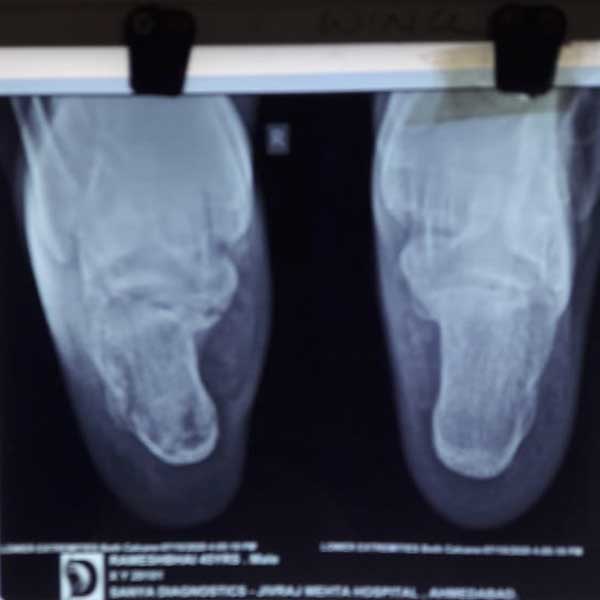

A male patient, aged 58 years had been diagnosed to have Closed comminuted fracture calcaneum . Closed reduction and percutaneous fixation done with CC Screw.

Pre-Operative

Post-Operative